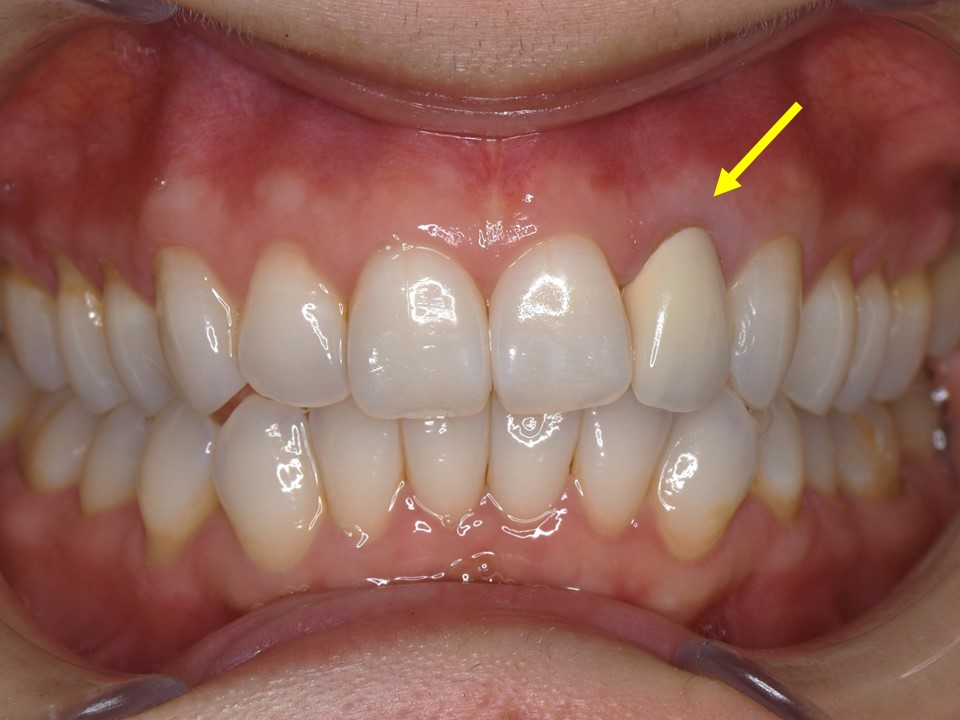

初診時口腔内。左側側切歯(⇒)のブラックマージンを主訴に来院。セラミッククラウンの色も透明感が無く、審美的な改善を希望。

ジルコニアオールセラミッククラウンによる再補綴を行った。当然ながら、歯肉圧排(2重圧排)とシリコン印象による精密印象を行っている。

歯の色合い、歯茎の反応も良く、自然な感じで仕上がっている。